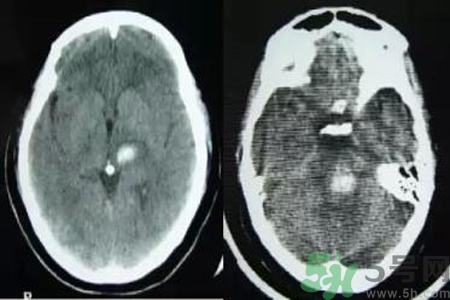

腦出血也稱腦溢血。顧名思義,腦出血是指腦實質內(nèi)的血管破裂,血液溢出即為腦出血。那么腦出血的發(fā)病因素是什么?腦出血的并發(fā)癥有哪些?

引起腦出血的病因很多,最常見的病因是高血壓動脈粥樣硬化,其次為先天性腦血管畸形或動脈瘤、血液病、腦外傷、抗凝或溶血栓治療、淀粉樣血管病等引起的腦出血。根據(jù)病因分類如下。

微動脈瘤破裂

因腦內(nèi)小動脈壁長期受高血壓引起的張力影響,使血管壁薄弱部位形成動脈瘤,其直徑一般500μm。高血壓患者的腦內(nèi)穿通動脈上形成許多微動脈瘤,多分布在基底核的紋狀動脈、腦橋、大腦白質和小腦中直徑在100~300μm的動脈上。這種動脈瘤是在血管壁薄弱部位形成囊狀,當血壓突然升高時,這種囊性血管容易破裂造成腦出血。